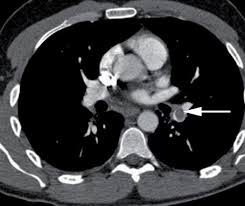

Health notes: Pulmonary embolism

A pulmonary embolism or blood clot on the lungs is a serious and potentially life-threatening condition. However, if treated, most patients will make a full recovery. A pulmonary embolism is a blood clot that has entered the lungs. ... read more